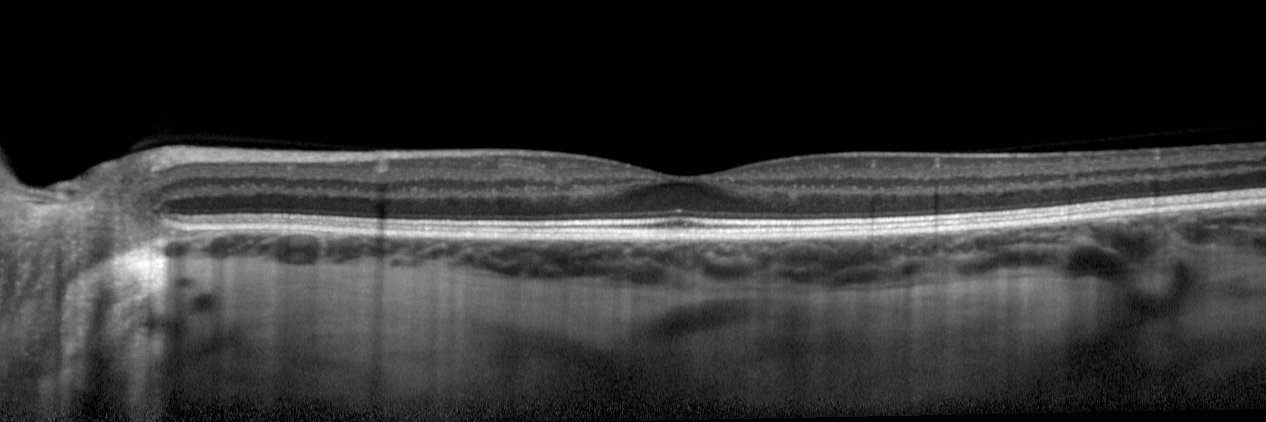

Zhihong Jewel Hu et al. @DohenyEye @AMD_histo_lab investigate the relationship between delayed rod-mediated dark adaptation and the status of outer retinal bands on OCT in early and intermediate AMD. doi.org/10.1167/iovs.6…